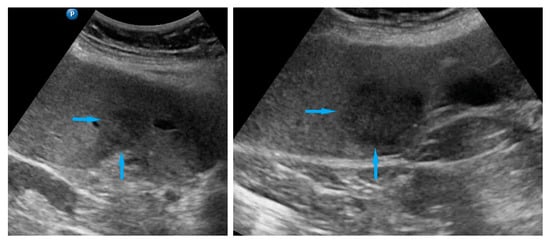

| Omentum | Focal infiltration of omentum: hypoechogenic nodules with discrete vascularization. Diffuse infiltration: omental cake appears as a nodular, perfuse, and non-peristaltic tumor that is located between the anterior abdominal wall and bowel loops. | Figure 1 | Video S1 |

| Small bowel mesentery root | Involvement is suspected when bowel loops have poor mobility and are “fixed together” in the dynamic ultrasound examination with a cauliflower-like image. | Figure 2 | Video S2 |